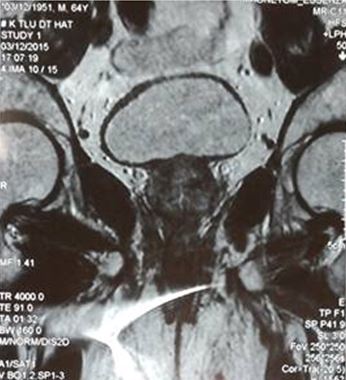

• Siêu âm, MRI tiểu khung tiền liệt tuyến to khoảng 25 g, khối u TLT chưa xâm lấn túi tinh

Trên hình ảnh MRI, khối u tuyến tiền liệt ranh giới rõ, bắt thuốc mạnh, kích thước 15 mm, chưa xâm lấn vỏ bao và túi tinh 2 bên.

• MRI tiểu khung: khối u TLT chưa xâm lấn túi tinh

Hình ảnh MRI: khối u tuyến tiền liệt ranh giới không rõ, ngấm thuốc sau tiêm, kích thước 12 x 15 mm, chưa xâm lấn vỏ bao và túi tinh